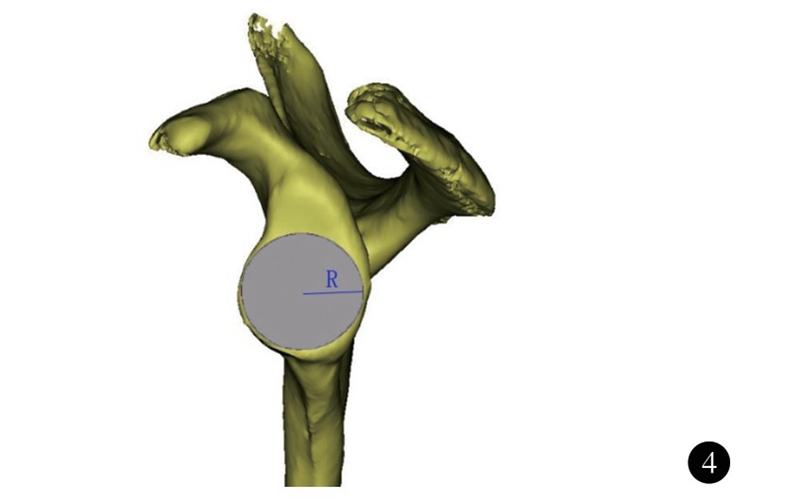

肩关节的活动主要由盂肱关节完成,为典型的球窝关节(杵臼关节) ,由肱骨头和肩胛盂构成。既往对肩关节的研究的重点集中在肩袖、关节囊韧带以及盂唇等结构,对肩关节的功能、稳定具有重要意义。随着中国社会老龄化的发展,肩胛盂骨性结构改变所带来的问题日趋严重,包括关节盂的缺损、退变。因此,了解肩胛盂的正常解剖结构,有助于对肩关节复杂损伤、疾病的治疗。肩胛盂的解剖结构包括肩胛盂关节面以及肩胛盂体部。肩胛盂体部(glenoid vault)是指肩胛骨包括肩胛盂表面及向内至肩胛冈外缘、喙突基底内缘的部分(图1)。这一区域骨量少,位置深,结构复杂。虽然传统尸体解剖研究可用于测量肩胛骨表面解剖学参数,但难以精确描述和测量,尤其是肩胛盂体部。随着电子计算机技术的不断发展和三维重建技术的进步,对肩胛盂骨性解剖结构的测量有了新的方法。研究肩胛盂骨性解剖学结构,可为肩胛盂内固定物和肩关节假体设计提供指导依据。

图1 肩胛盂体部形态(深色部分)示意图。包括肩胛盂表面及向内至肩胛冈外缘、喙突基底内缘的部分